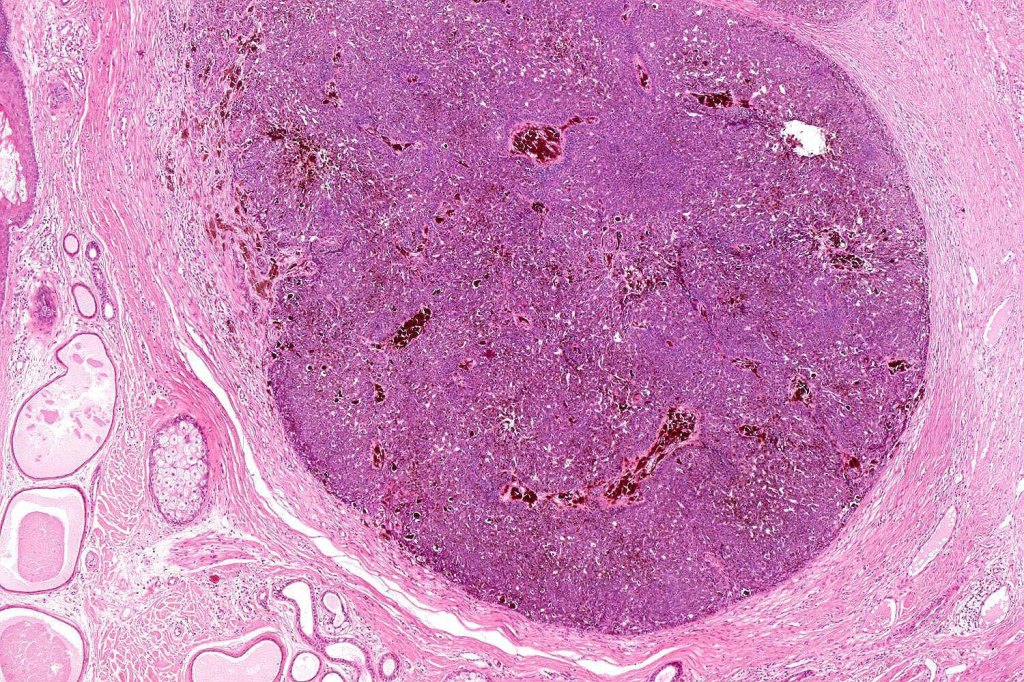

•Sharply circumscribed nodule, sometimes with a pseudocapsule

•Uniform basaloid cells with peripheral palisading and often marked mitotic activity

•Absence of retraction artifact and mucin deposition

•Pigmented variant